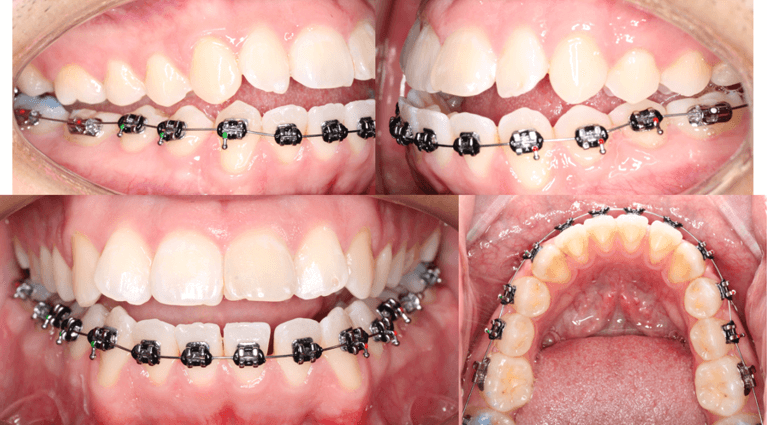

Segunda cita. Colocacion de brackets MBT slot .022 superior incluyendo primeros y segundos molares. Arco nitinol .14 superior e inferior. Ligadura individual en laterales superiores.

Fig 6. Seguimiento fotografico

Quinta cita. Aumento de topes oclusales en segundos molares inferiores. Cambio de arco nitinol .16 superior. Arco de acero inoxidable .16 inferior. En arcada inferior se realizó la siguiente biomecánica: colocación de ligadura metálica continua de 46-43 y 36-33 en conjunto de una cadena elástica de 43-33.

Fig 7. Seguimiento fotografico

Septima cita. Ya se encontraba el paciente con ligadura de contencion del 33-43 para prevenir la aparicion de los tremas. Arco 16x16 nitinol superior e inferior. Stripping del 13, 12, 11, 21, 22, 23.

Fig 8. Seguimiento fotografico

Novena cita. Arco 16x22 nitinol superior. Arco 16x22 acero inoxidable inferior. Ligas intermaxilares clase III 3/16 4.5oz.

Fig 9. Seguimiento fotografico